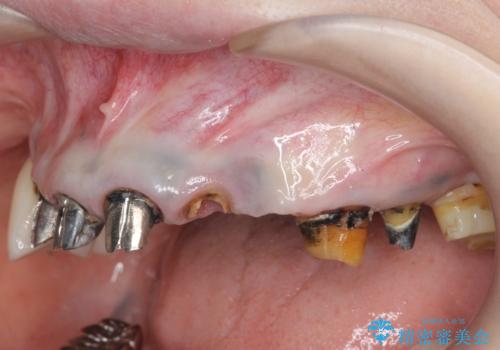

- 「歯がぐらぐらして噛めない。」、全体的な治療を希望されて来院されました。

クラウン・コアを除去したところ支台となる歯は破折し残すことが難しい状況でした。

抜去を行ったのち、インプラント治療を計画しますが骨量が少ないため、まず骨の造成を行ったのちインプラントを埋入していく治療計画としました。